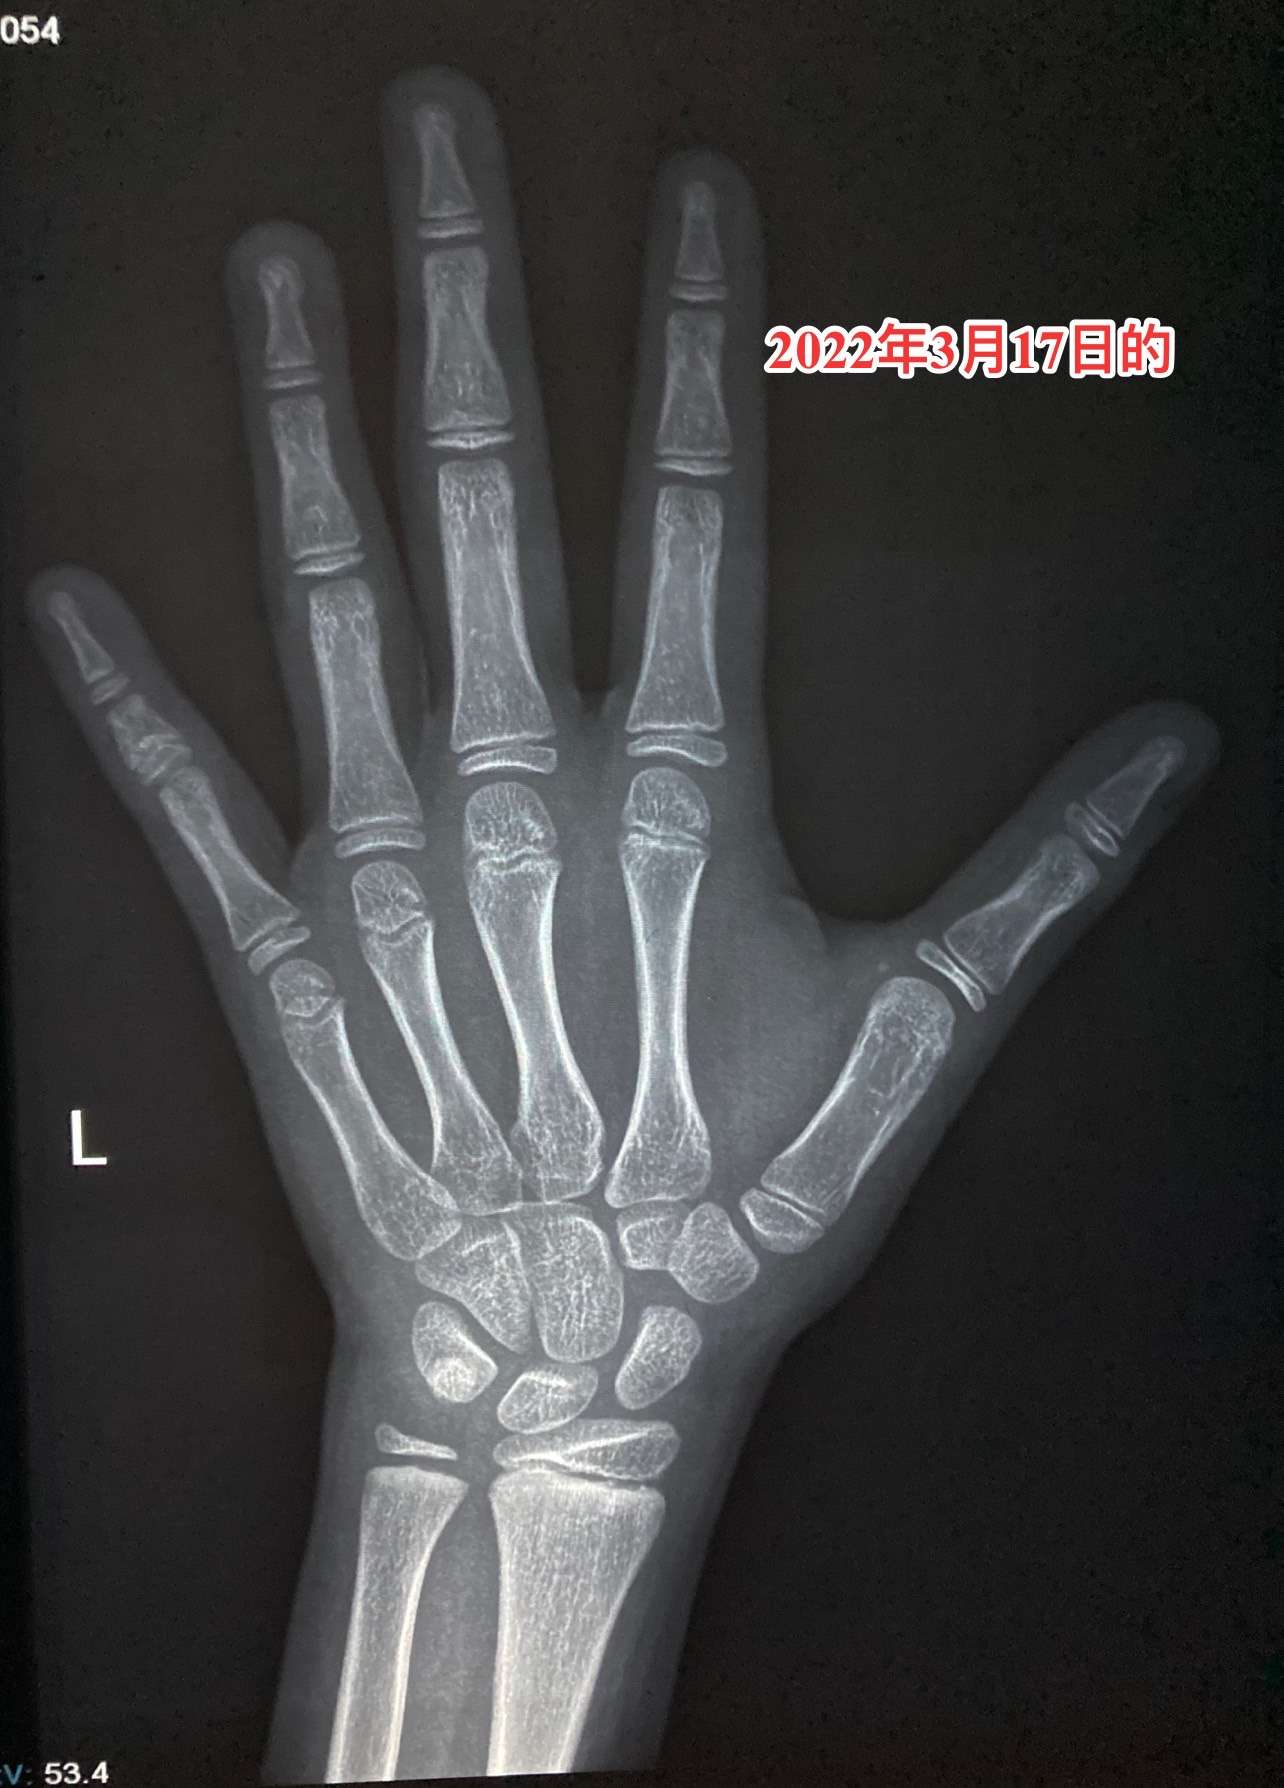

籽骨骨龄

外医院一看籽骨就13岁余医生用中华05计分法看骨龄125

的,十三岁半应该还是不够,尺骨骨骺稍显稚嫩,第一掌指关节区籽骨出现